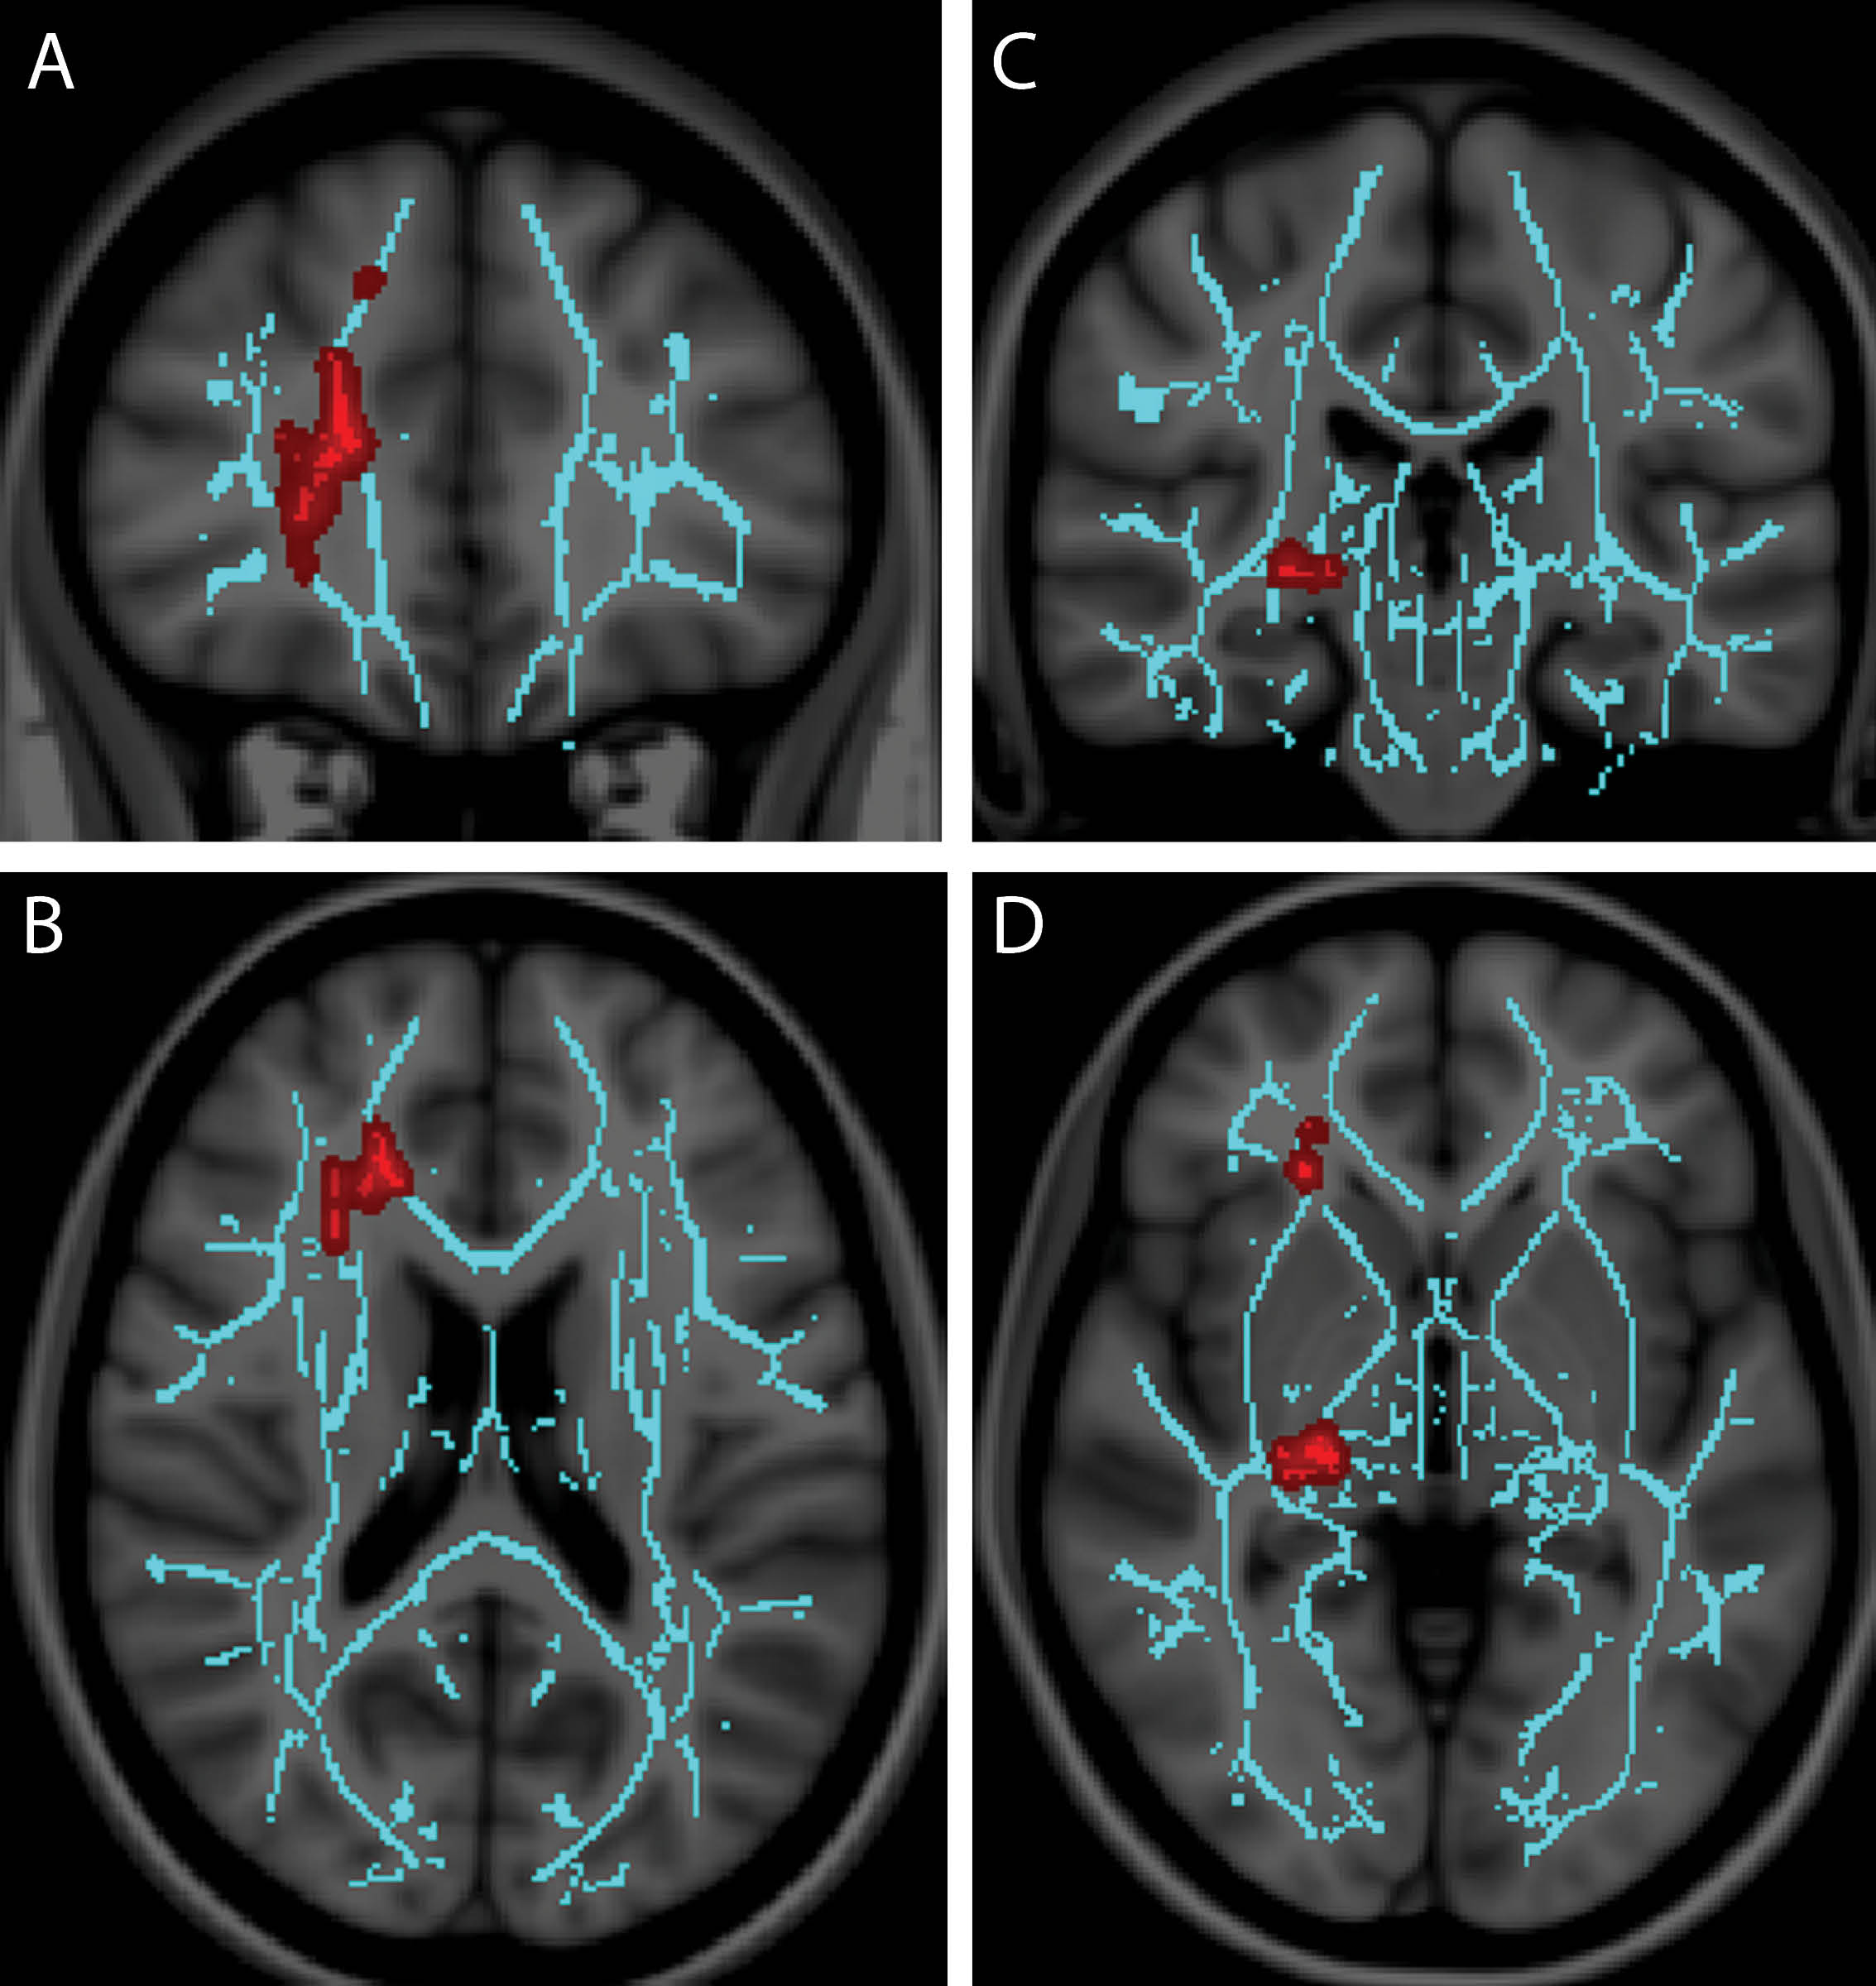

Dr. Alhilali was lead author on a retrospective study that identified a central axonal injury component in patients with mTBI and vestibulopathy, who were imaged with diffusion-tensor imaging (DTI). The findings suggest a role for DTI in mTBI diagnosis, with a quantitative biomarker to aid in that diagnosis. The results were published in the July 2014 issue of Radiology.

Researchers reviewed 30 patients with mTBI and vestibular symptoms and 25 patients with mTBI and ocular convergence insufficiency. Fractional anisotropy (FA) maps were generated as a measure of white matter integrity and analyzed with tract-based statistics regression analysis using a general linear model. DTI abnormalities were correlated with symptom severity, neurocognitive test scores and time to recovery.

Dr. Alhilali and colleagues found that patients with vestibular symptoms had decreased neurocognitive test scores and FA values in the cerebellum and fusiform gyri. Patients suffering from convergence insufficiency also exhibited diminished neurocognitive test scores with FA values in the right anterior thalamic radiation and right geniculate nucleus optic tracks.